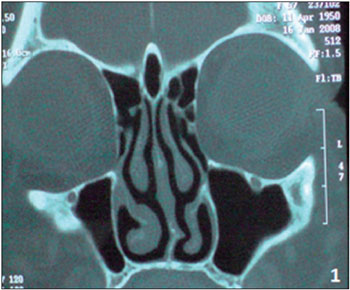

CASE STUDY #1A 57-year-old female patient sought advice from the Specialized Service in Otolaryngology in June 2008, complaining of a frontal headache that had been present for the last year. The patient reported previous drug treatments for sinusitis including azithromycin for 5 days, amoxicillin for 10 days, and a combination of amoxicillin and clavulanate potassium for 10 days. However, she always experienced recurrence and progressive worsening of her symptoms. Examination with video-endoscopy showed hypertrophy of the lower and middle turbinates bilaterally associated with septal deviation in the left nasal cavity. A computed tomography (CT) scan of the paranasal sinuses and nasal cavity in the axial, coronal, and sagittal planes with a bone window of 2500-3500 rads was requested, which identified pneumatization of the crista galli with mild mucosal thickening in the interior (Figure 1). This finding indicated endoscopic surgery through the transseptal approach in the left nasal cavity for drainage and cleaning of the pneumatized crista galli (Figure 2).

Figure 1. Preoperative coronal section CT scan showing crista galli pneumatization with mucosal thickening.